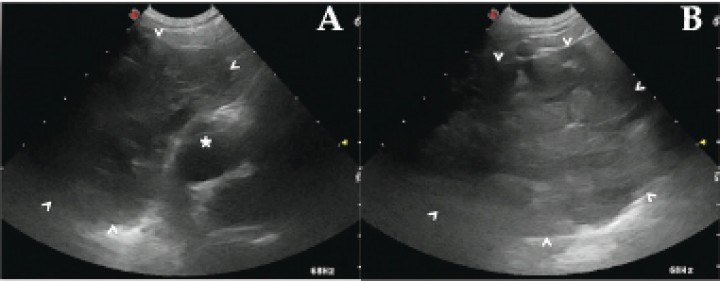

Se realizó ecografía para caracterizar la masa mediastínica craneal y la efusión pleural, observando una gran masa redondeada, de márgenes bien definidos, hipoecoica y de aspecto glandular, craneal al corazón. A la exploración Doppler no se evidenció vascularización significativa. La pequeña cantidad de líquido pleural observado en las radiografías era hipoecoico, sin reactividad de las membranas pleurales. El corazón no presentaba alteraciones reseñables. (Fig. 3). En base a la imagen ecográfica se acotó el diferencial a hematoma, granuloma y neoplasia tímica. La ausencia de neovascularización, la arquitectura glandular y la historia clínica hacen más probable un hematoma tímico.

<p>(<strong>A</strong> y <strong>B</strong>) Cortes longitudinales de la ecografía torácica a diferentes niveles de tórax craneal. Se observa una gran masa heterogénea de aspecto glandular (puntas de flecha) en contacto con el polo craneal del corazón (*).</p>

(A y B) Cortes longitudinales de la ecografía torácica a diferentes niveles de tórax craneal. Se observa una gran masa heterogénea de aspecto glandular (puntas de flecha) en contacto con el polo craneal del corazón (*).